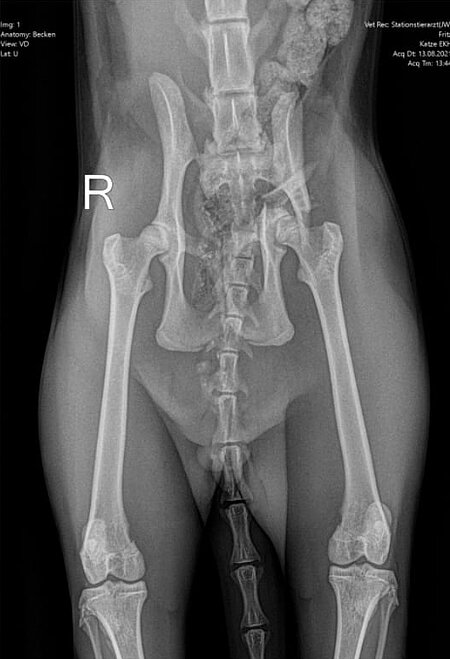

Am Abend des 8. August 2021 kam Fritz nicht nach Hause. Gegen 19 Uhr erreichte mich der Anruf von einem Tierarzt, der mir mitteilte, dass Fritz schwerverletzt bei ihm abgegeben worden sei und es ihm nicht gut gehe. Unser junger, roter Kater Fritz war vermutlich angefahren worden und konnte seine Hinterläufe nicht mehr bewegen. Wir brachten ihn sofort nach Weilheim in die Tierklinik, wo das erste Röntgenbild einen beidseitigen Bruch des Beckens zeigte. Fritz wurde stationär aufgenommen und mehrere Tage intensiv behandelt, bevor er operiert werden konnte. Nach der Entlassung aus der Klinik folgten sechs Wochen Bewegungseinschränkung in einem Käfig. Er durfte sich weder im Haus noch im Garten frei bewegen. Danach blieb ihm der Freigang in der Natur noch für weitere vier Wochen versagt. Fritz war sehr geduldig und so brav, seine Katzenfreundinnen Mona und Lisa leisteten ihm Gesellschaft. Unsere Streicheleinheiten waren unzählbar... Die Operationswunden sind sehr gut verheilt, die Verletzungen machen keine Probleme mehr. Der junge Fritz ist wieder „ganz der alte“ und erfreut sich eines wundervollen Katzenlebens!

Bei der Einlieferung war der Kater in einem schweren Schockzustand, sodass sein Kreislauf zunächst mit Infusionen und Schmerzmedikamenten unter dem Rotlicht stabilisiert werden musste. Nachdem eine leichte Besserung eingetreten war, wurde eine Ultraschalluntersuchung des Bauchraums durchgeführt, um lebensbedrohliche innere Blutungen auszuschließen und ein erstes röntgenologisches Screening in Form von zwei Übersichtsaufnahmen. Dabei stellte sich heraus, dass Fritz neben den schon erwähnten Beckenfrakturen, die häufig mit einem massiven Blutverlust in den Beckenraum einhergehen, auch leichte Lungenverletzungen erlitten hatte. Unter der Schocktherapie besserte sich das Allgemeinbefinden des Patienten innerhalb weniger Tage. In den regelmäßigen Laborkontrollen war jedoch am 11. August eine ausgeprägte Anämie erkennbar, weshalb Fritz noch eine Bluttransfusion erhielt.

Am 13. August, also fünf Tage nach dem Unfall, entschied man sich dann zur Operation, da die Verlaufsuntersuchung dank der wiedergewonnenen Reaktionsfähigkeit des Patienten jetzt den Verdacht einer begleitenden Verletzung des rechten Ischias Nerven aufkommen ließ. Durch Vorbiegen einer Knochenplatte an einem Beckenmodell wurde der Eingriff sorgfältig vorbereitet, um die Operationszeit möglichst kurz halten zu können.

Röntgenbilder mit freundlicher Genehmigung Tierklinik Weilheim.